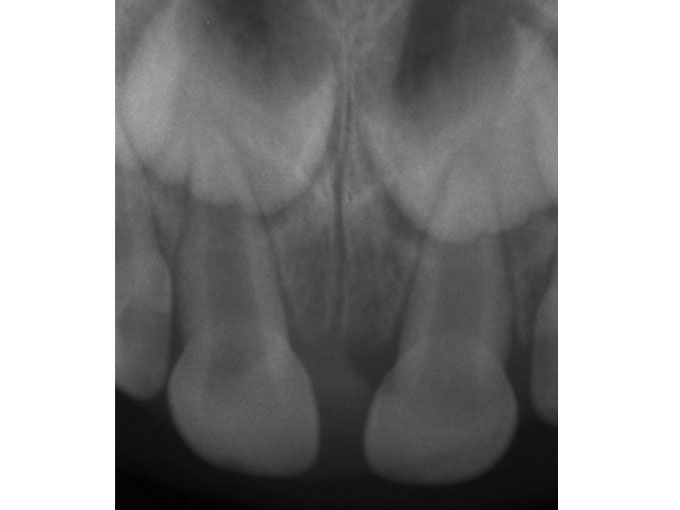

En la imagen superior se ven los incisivos temporales de Gael, el de la derecha que es en realidad su paleto izquierdo es el que ha recibido el golpe.

En la radiografía se comprueba que está entero, que no se ha fracturado la raíz. Los "globos" que se ven encima de ellos es el germen de los dientes permanentes que están en formación. Por suerte, en este caso no hay que hacer nada con la pieza dañada. El diente está bien y prácticamente ha vuelto a recobrar su color original.